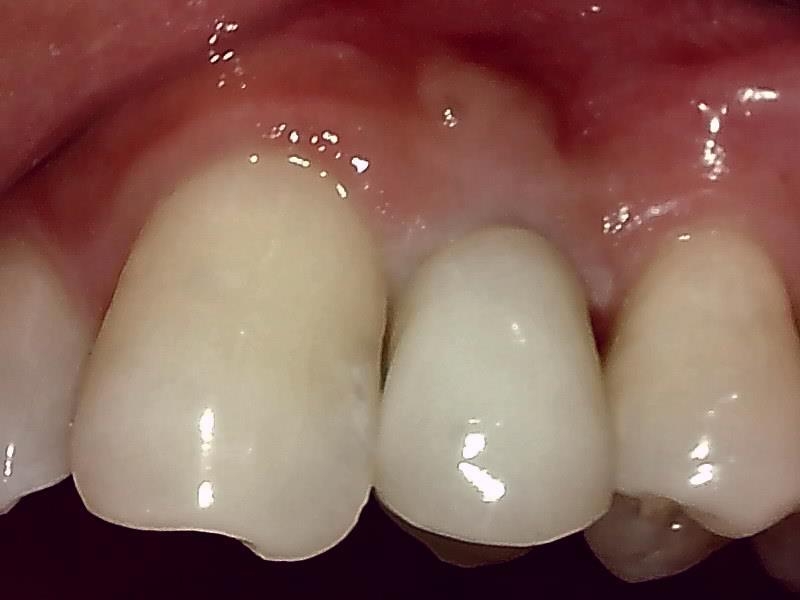

歯肉の整形 (左上)とても綺麗な良い歯肉の状態です。